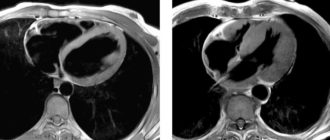

Кт и мрт диагностика дефекта межпредсердной перегородки 1/3 всех ВПС дефект межпредсердной перегородки сердца